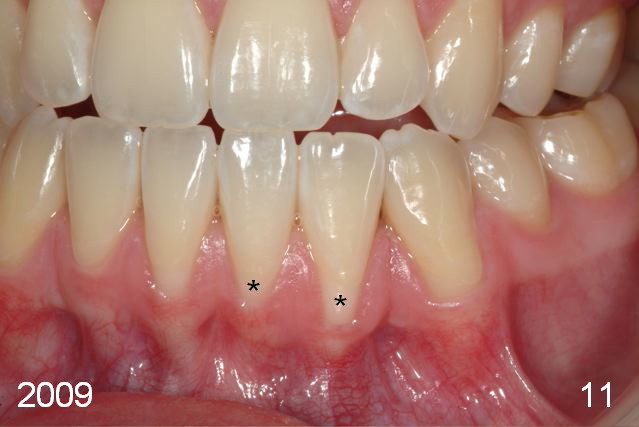

The labial gingival recession of the lower anterior teeth (Fig.11) was treated with gingival graft (Fig.5,12*). One of the last things Chip Webster did before he died! God rest his soul.